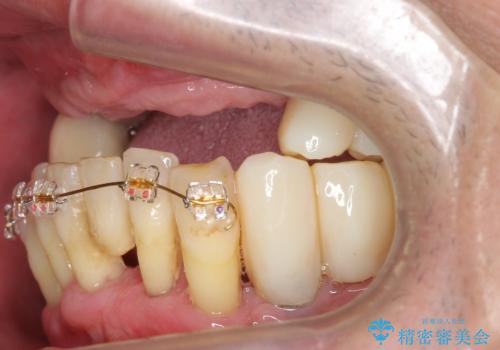

- 歯がないまま放置しており咬めないことを主訴に来院された患者様です。

仕事が忙しくなかなか自分のことに気が回らなかったそうですが、どんどん歯が抜け落ちて「もう限界だ!」と思い受診を決断したとのことでした。

精査したところ、全顎的な重度の歯周病により上顎前歯はすべて欠損していました。

禁煙指導と歯周病治療後、インプラント治療を行うことにしました。

咬合関係がⅢ級(受け口)のため唇側に骨増生を行ったのちインプラント埋入(右上31左上3)を行いました。

治療途中で患者様が喫煙を再開され、最もタバコの影響を受けやすい上顎前歯部(右上31)インプラント周囲の骨吸収と少量の排膿を認めました。